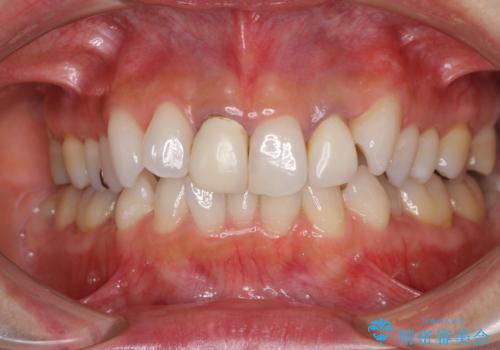

- 20年ほど前に被せた前歯のメタルボンドクラウンの色合いを気にして来院された患者様です。

2歯をオールセラミッククラウン(ジルコニアクラウン)にて補綴することとしました。

裏打ちが金属の場合、どうしても金属色を遮蔽しないとならないため、透明感のない色合いとなってしまいます。

土台の金属はグラスファイバーを含有したものに、クラウンの土台は強化セラミックとすることで、自然な前歯に仕上がりました。